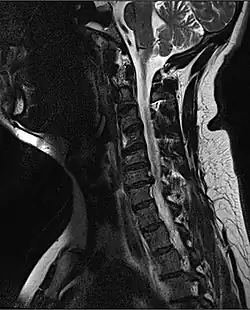

![]() | |

| MRI of a fractured and dislocated cervical vertebra (C4) in the neck that is compressing the spinal cord | |

Diagnosis

A radiographic evaluation using an X-ray, CT scan, or MRI can determine if there is damage to the spinal column and where it is located.[10] X-rays are commonly available[89] and can detect instability or misalignment of the spinal column, but do not give very detailed images and can miss injuries to the spinal cord or displacement of ligaments or disks that do not have accompanying spinal column damage.[10] Thus when X-ray findings are normal but SCI is still suspected due to pain or SCI symptoms, CT or MRI scans are used.[89] CT gives greater detail than X-rays, but exposes the patient to more radiation,[91] and it still does not give images of the spinal cord or ligaments; MRI shows body structures in the greatest detail.[10] Thus it is the standard for anyone who has neurological deficits found in SCI or is thought to have an unstable spinal column injury.[92]